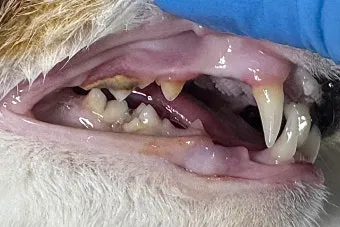

둘째, 잇몸에 붉은 테두리(발적)가 생기고 치경부 주변으로 붓기가 나타납니다. 하얀 타르 같은 치석 띠가 보이면 진행 중이라는 뜻입니다.

셋째, 침에 약간의 혈색이 돌거나 음식을 먹다 떨어뜨립니다. 가끔 앞발로 입을 문지르는 행동도 관찰됩니다.

넷째, 구내 점막에 궤양성 병변이 보일 수 있습니다. 특히 작은 혓바닥 옆면과 구강 뒤쪽 아치 부위가 민감합니다.

고양이 치주염과 구내염, 치흡수성 병변은 겹치는 부분이 있습니다. 그러나 통증 위치와 병변 모양에서 차이가 보입니다.

구내염은 보통 구강 뒤쪽 아치의 넓은 발적과 심한 통증을 동반하고, 치흡수성 병변은 치경부가 움푹 파이거나 치관이 잘게 부서지는 양상이 특징입니다. 사진 기록이 큰 힘을 발휘합니다.